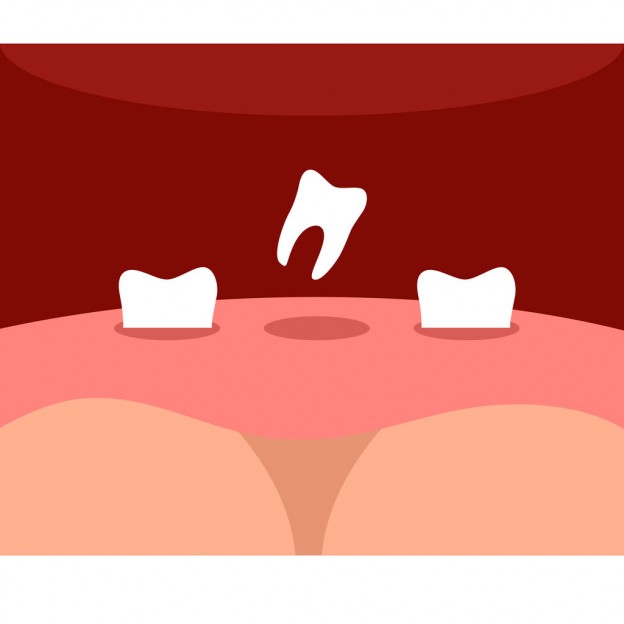

An implant is an artificial tooth root made of titanium metal. The fixture is surgically embedded into the jaw bone and after a period of time to heal an abutment is placed. The abutment part of the implant sticks out of the gums and is attached to the fixture. Soon after a crown can be made to fit onto the abutment. Dental implants can replace a single tooth or several teeth. If you are missing all of your teeth implants can also be used to support a full bridge or denture. Dental implants allow people with missing teeth to be able to smile, speak, and chew well and comfortably.

What is a Dental Implant?